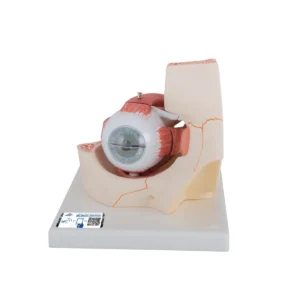

UK 3B Scientific manufacture anatomical models and teaching aids for medical education. 3B Scientific manufacture Medical Simulators, Human anatomy models and charts for universities, schools & health boards.

With competitive value and quality products 3B Scientific equipment has become very popular. Their smart app and other advanced technologies allows students more anatomical information and learning than ever.